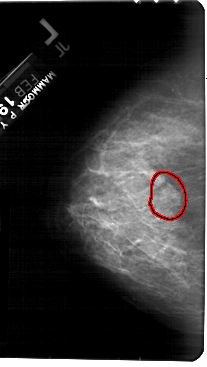

A_1397_1.RIGHT_CC

RIGHT_CC LINES 5371 PIXELS_PER_LINE 2761 BITS_PER_PIXEL 12 RESOLUTION 43.5 OVERLAY

FILE: A_1397_1.RIGHT_CC.OVERLAY

TOTAL_ABNORMALITIES 1

ABNORMALITY 1

LESION_TYPE MASS SHAPE LOBULATED MARGINS OBSCURED

ASSESSMENT 4

SUBTLETY 3

PATHOLOGY BENIGN

TOTAL_OUTLINES 1

BOUNDARY